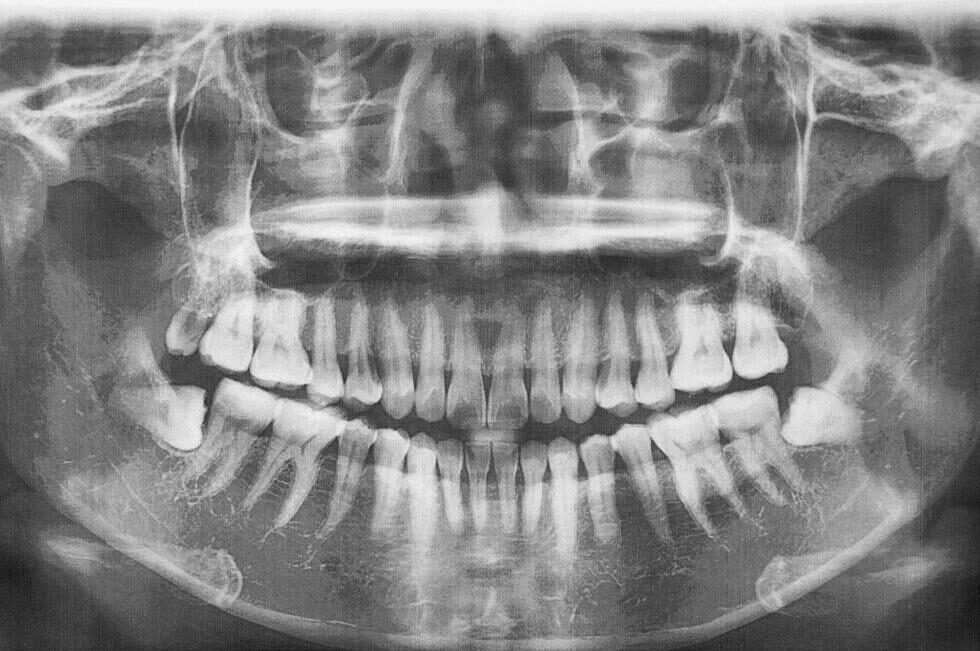

- 検査・診察……口腔内の診察とレントゲン撮影を行う(※炎症が強い場合は抜歯は後日となる)